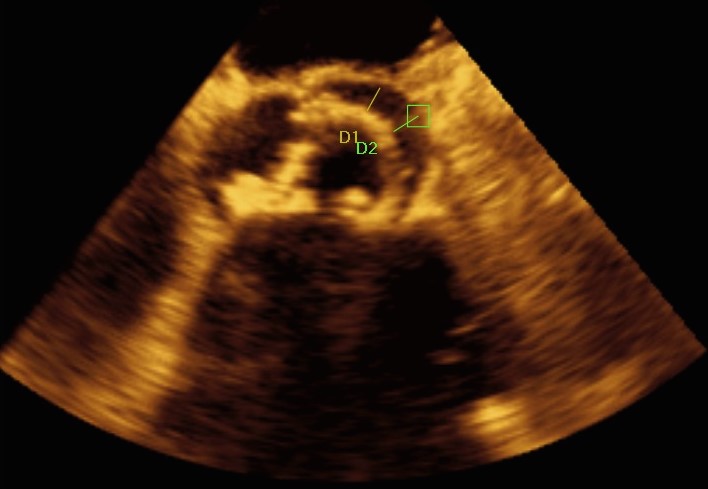

After creating an artero-venous loop between a transeptal and an arterial system, two vascular plugs (AVP III 10×5 and AVP III 8×4 ) were positioned and released, with their final position checked at TEE.